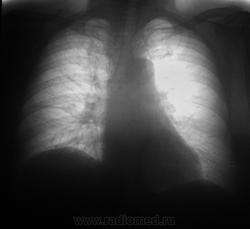

Через полтора года...

Мезотелиома!?

Пациент полтора года выращивал это ходил? По первым ФЛГ норму поставили?

Выросло,однако.